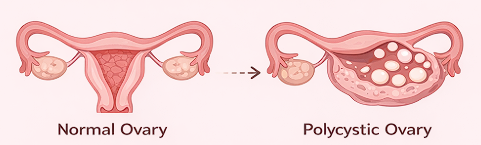

Women’s health requires a thoughtful and personalized approach at every stage of life. Our gynecology services are designed to diagnose, manage, and treat a wide range of gynecological conditions with accuracy, compassion, and advanced medical expertise. We provide comprehensive care for issues such as menstrual irregularities, pelvic pain, hormonal imbalances, reproductive health concerns, infections, fibroids, ovarian cysts, and other common and complex gynecological conditions.

Using modern diagnostic techniques and evidence-based treatments, our team focuses on identifying the root cause of symptoms rather than just managing them temporarily. Each patient receives an individualized treatment plan based on her medical history, symptoms, and overall health goals. From routine check-ups and preventive screenings to specialized treatments and minimally invasive procedures, we aim to deliver safe and effective care tailored to each individual.